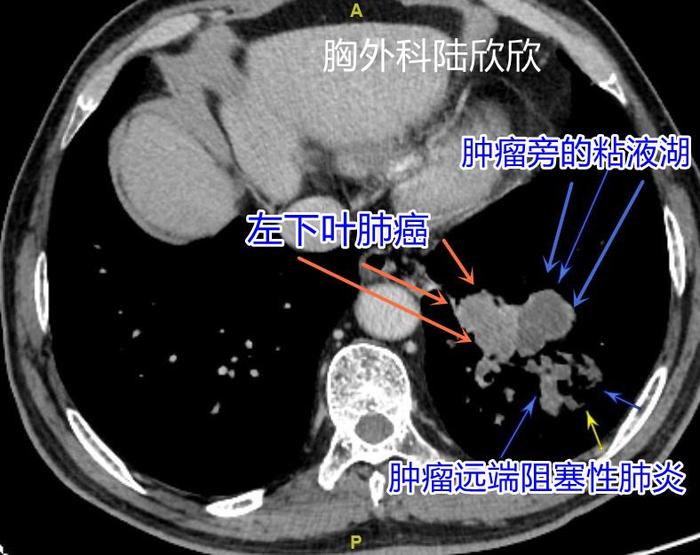

上图,左下叶肺癌的下级可见液性暗区,为肿瘤旁的粘液湖,是肺里面的粘液被肿瘤阻挡,排不出来,形成的小块液性区域。肿瘤远端还有阻塞性肺炎,用靠后的三个箭头标示。